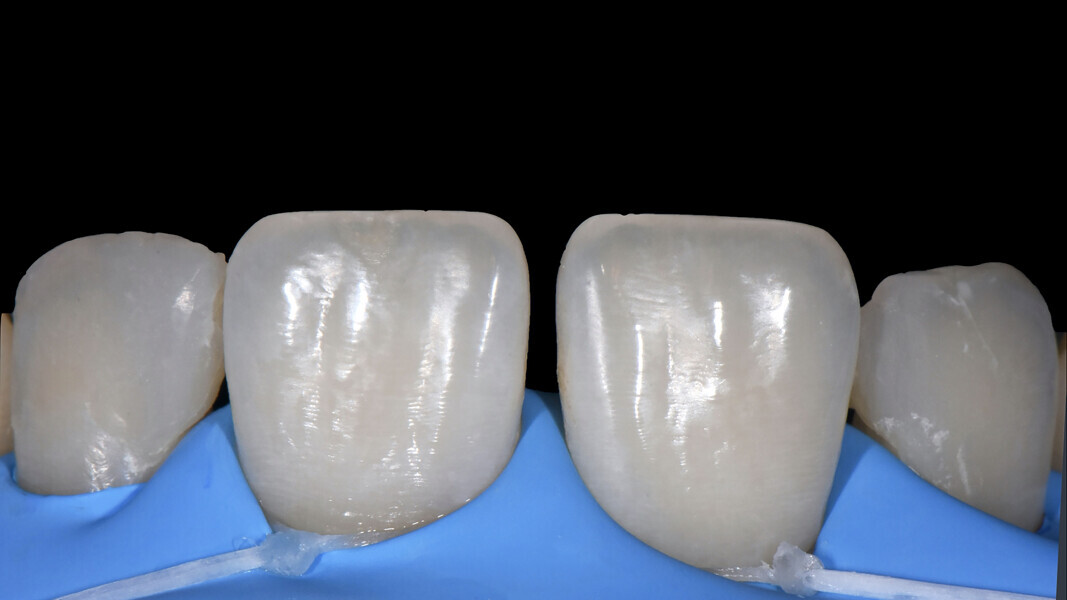

Fig. 12: Marked transition lines.

Texturing of the surface Transition lines were drawn on the vestibular surfaces of teeth #12–21 using a pencil (Fig. 12) to provide guidance for the contouring.12 Lastly, the texture steps were performed (Fig. 13), creating vertical texture with a rough appearance for the demarcation of vestibular features and giving an appropriate curvature to the area of the contact point;13 as well as creating micro-texture: after proper mirror polishing, restorations can be made brighter depending on how the incident light is dispersed, absorbed and reflected on the irregular vestibular surface geometry (Figs. 14 & 15).14

Fig. 13: Achievement of the surface texture.

Figs. 14a & b: Control and smoothing of the marginal contour.

Fig. 15a: Control of restoration.

Fig. 15b: Control of restoration.